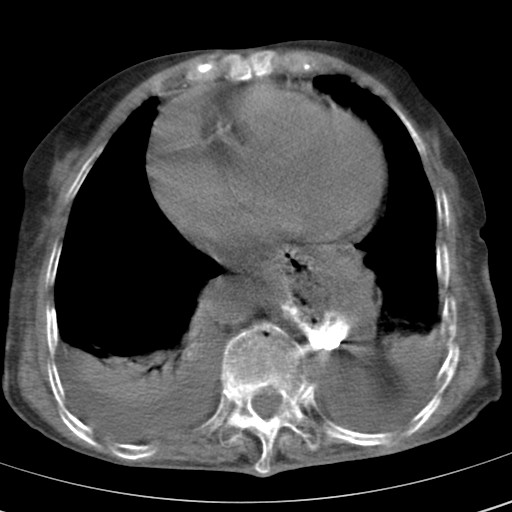

女,93岁,摔伤后检查。

右肺炎症,心功能不全伴双侧胸腔积液,右下肺膨胀不全,食管裂孔疝,冠脉钙化,心包少量积液,左侧肋骨骨折,请上传骨窗.

食管裂孔疝

右侧锁骨\\肩胛骨骨折、右侧湿肺,心功能不全伴双侧胸腔积液,右下肺膨胀不全,左膈破裂或食管裂孔疝,冠脉钙化,心包少量积液,请上传骨窗.

右肺炎症,心功能不全伴双侧胸腔积液,右下肺膨胀不全,食管裂孔疝,冠脉钙化,心包少量积液,左侧肋骨骨折,右肩甲骨粉碎性骨折。93岁,高寿哇!

右肺炎症,心功能不全伴双侧胸腔积液,右下肺膨胀不全,食管裂孔疝,冠脉钙化,心包少量积液,左侧肋骨骨折,右肩甲骨粉碎性骨折。